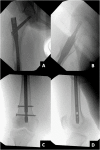

The COVID-19 pandemic has necessitated increased use of telemedicine for diagnosis and management of musculoskeletal disorders. We describe the virtual/telemedicine encounter and management of a patient with knee pain initially diagnosed as gonarthrosis but that actually resulted from an impending pathologic fracture of the femur. Definitive diagnosis and treatment occurred only after completion of the impending fracture. The multiple factors making telemedicine encounters challenging which contributed to this outcome are highlighted. Orthopedists need awareness of these challenges and must take steps to mitigate the risk of complications possible with continued increased utilization of telemedicine during this pandemic and beyond.